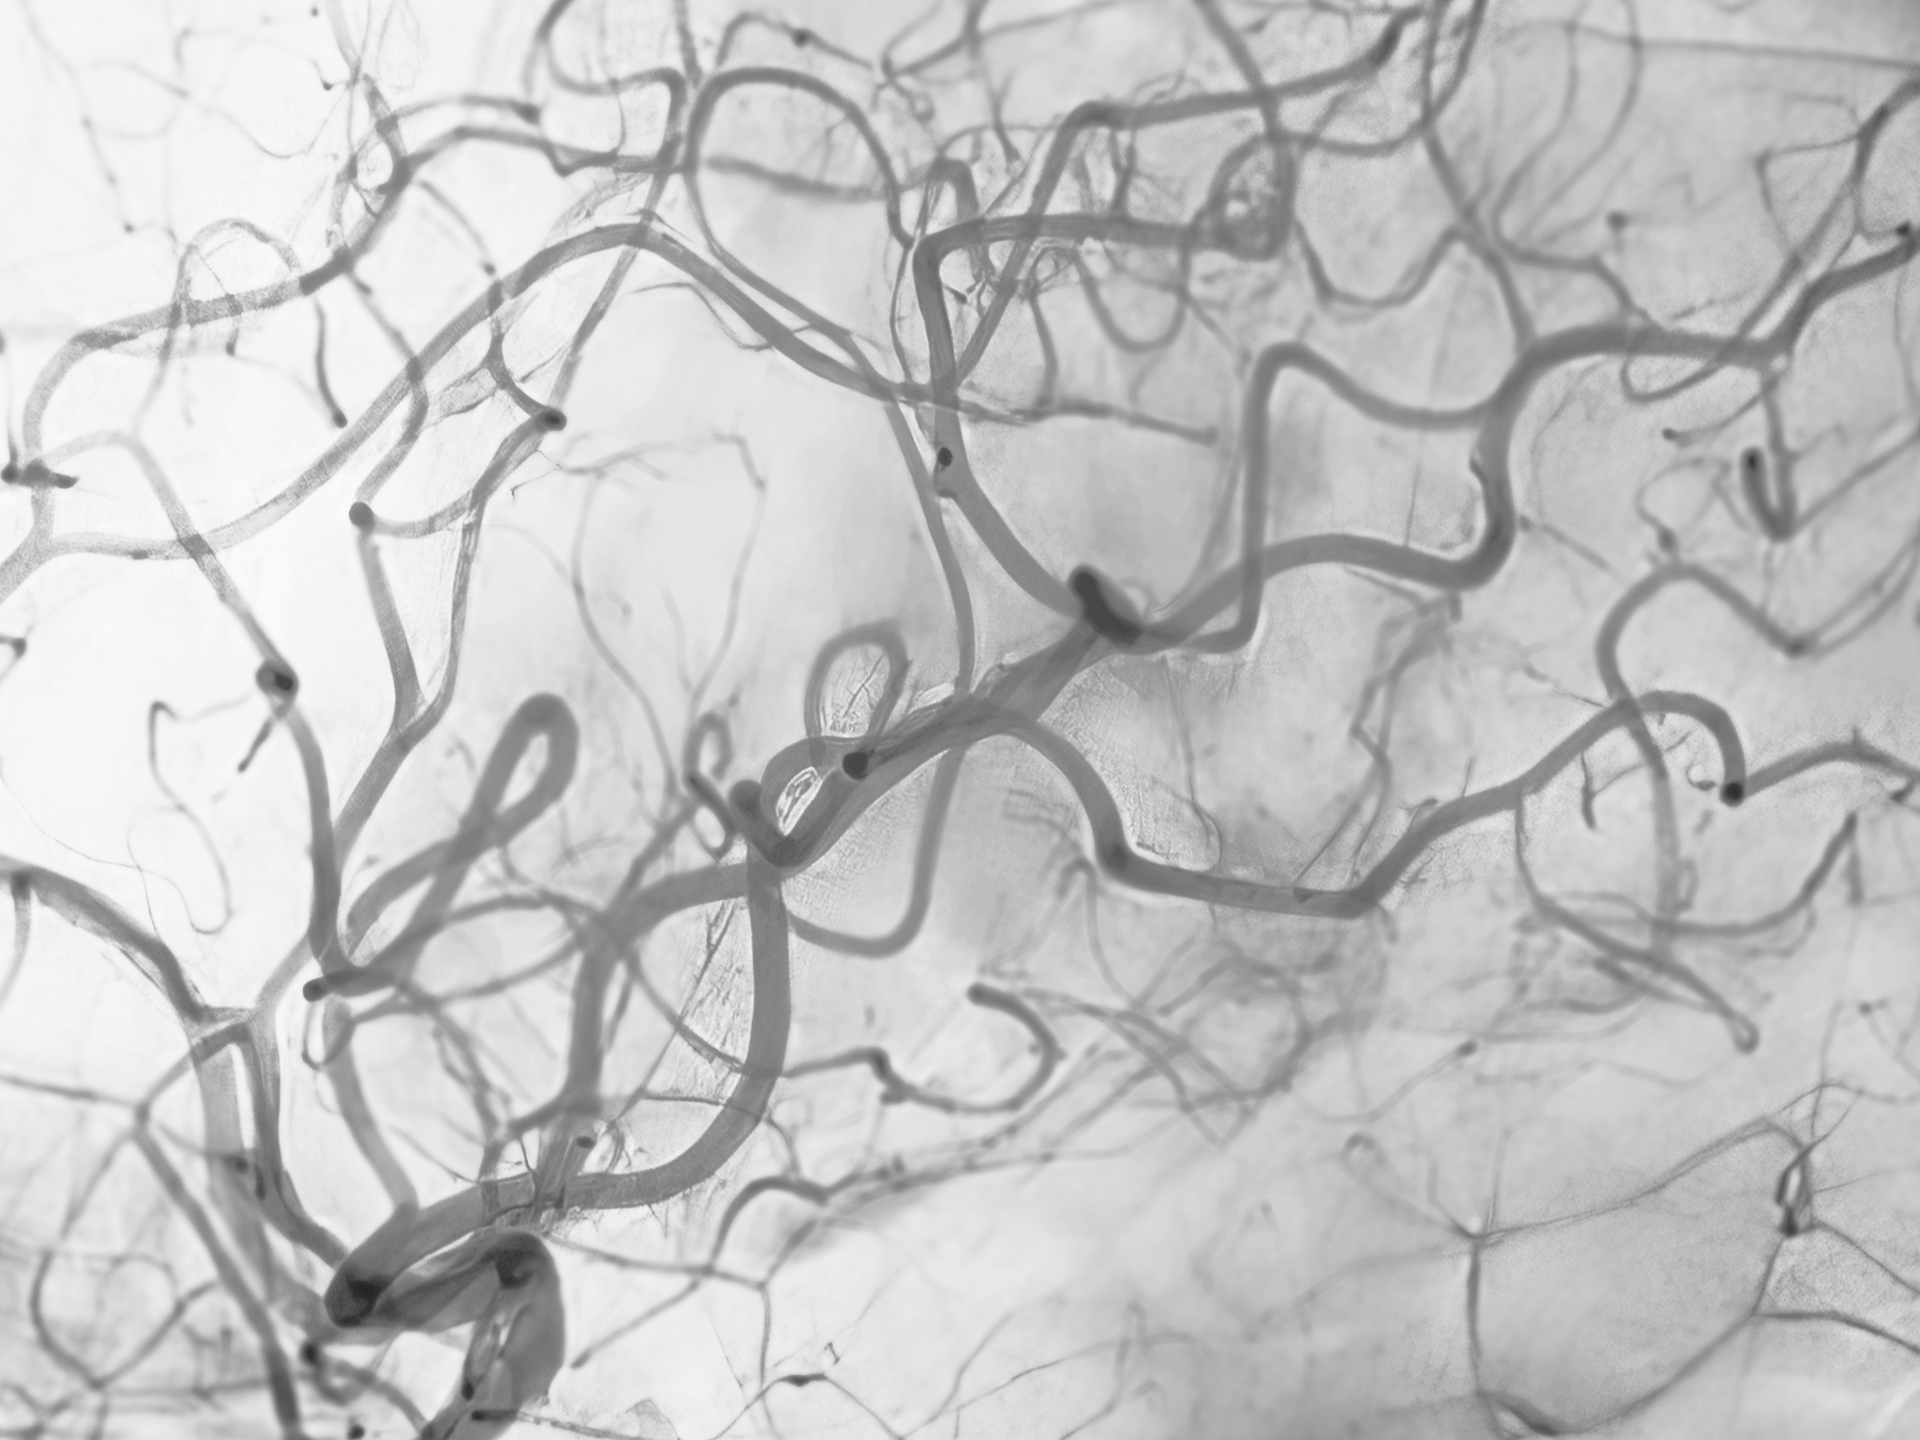

모세혈관 확장증,

하지정맥류와 어떤 관계가 있나요?

다리(종아리, 허벅지)에 나타나는 모세혈관 확장증(붉거나 푸른 실핏줄)은

단순히 피부 문제가 아닌 하지정맥류와 매우 밀접하게 연관되어 있습니다.

모세혈관 확장증은 겉으로 보기엔 실핏줄이 도드라져 보이기만 하지만

도플러(초음파) 검사 진행 시 하지정맥류의 초기 단계이거나

이미 하지정맥류가 진행되고 있는 경우가 높습니다.